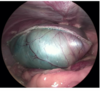

cystoscopy

- direct, magnified view of the mucosal surfaces of the bladder and urethra.

- allows retrieval of calculi or biopsy of bladder tissue, lithotripsy of bladder calculi, laser ablation of ectopic ureters, submucosal injection of collagen